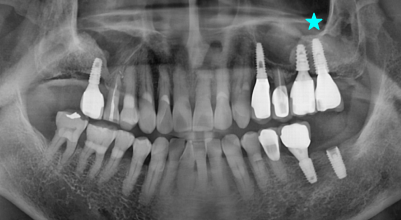

Internal Bone Level - Tapered

The IB-T implant system offers a flexible solution for all indications and esthetic outcomes. It is a submerged type implant that has an internal hex 11˚ taper connection. With tapered body design, it allows excellent primary stability, and it can be applied to any situation as it has various diameters, lengths and prosthetic line-up.